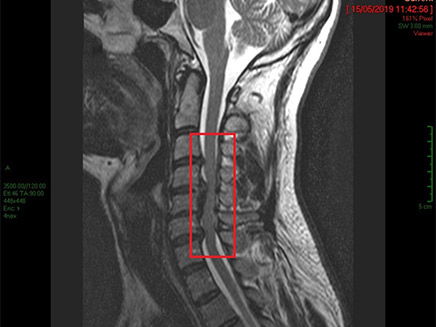

הצוות הרפואי בבית החולים בילינסון אליו פונה, זיהה בבדיקות חשש לפגיעה צווארית. בדיקת MRI שערך הצוות הרפואי אוששה את החשד שיש צורך בניתוח מורכב ודחוף בשל חשש משיתוק ואף סכנת חיים.

"הייתי צריך לכרות לו באופן מלא חוליה ולהחליף אותה ואת הדיסקים המקיפים אותה בחוליה מלאכותית", תיאר ד"ר אמיתי אמיר, מנהל היחידה לניתוחי עמוד שדרה במחלקה האורתופדית, בשיחה עם 'מאקו'. "תוך כדי הניתוח ניטרנו באמצעים מתקדמים את הפעילות העצבית שלו".